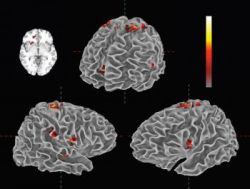

Druhý blok experimentu predstavovalo načúvanie. Vedci sledovali dobrovoľníkov, ktorých vybrali spomedzi milovníkov hudby – jednak „povrchovo“, zaznamenávaním správania, jednak „hĺbkovo“, zaznamenávaním mozgovej činnosti cez zobrazovanie pomocou funkčnej magnetickej rezonancie (fMRI). Celkove bolo dobrovoľníkov 125, 85 žien a 40 mužov vo veku 18-29 rokov. Z toho vedci 29 určili ako „hlbokých poslucháčov“ hudby. A z nich sa napokon na fMRI skenovaní zúčastnilo 21, 14 žien a 7 mužov vo veku 18-21 rokov. Načúvanie malo tri časti. V prvej dobrovoľníci v reálnom čase oznamovali svoje emócie pomocou špeciálneho softvéru. V druhej vedci použili fMRI – dobrovoľníci pokojne ležali v skeneri so zavretými očami a vypočuli si obidve verzie etudy bez toho, aby vyjadrili svoje emócie. Tie napokon v tretej časti, bezprostredne po fMRI, zaznamenali.

Vedci následne porovnávali mozgovú činnosť dobrovoľníkov pri počúvaní expresívnej i mechanickej verzie etudy, reakcie skúsených a menej skúsených poslucháčov a zmeny tempa s aktiváciami jednotlivých častí mozgu poslucháčov v reálnom čase. Potvrdilo sa, že spomenuté „ľudské“ prvky interpretácie expresívnej verzie priamo aktivovali mozgovú činnosť, súvisiacu s emóciami a vnímaním príjemných pocitov (tzv. centrum odmien). Výraznejšie pri skúsených poslucháčoch, ktorí síce neboli profesionálni hudobníci, ale trebárs spievali v zbore, alebo hrali zo záľuby sami či spoločne s ďalšími.

„Údaje z fMRI ukázali, že skúsených poslucháčov hudba akosi viac nabíja, hoci na základe iba týchto údajov nemôžeme povedať, či zvýšená aktivita ich neurónov vyplýva z ich predchádzajúcej skúsenosti s hudbou, alebo naopak vyhľadávajú hudobné zážitky, lebo im hudba spôsobuje väčšiu radosť,“ povedal Edward Large. Výskum doložil aj mozgovú aktivitu po interpretačných nuansách v reálnom čase. Jednak v motorických sieťach, ktoré sprostredkúvajú sledovanie rytmu hudby, jednak v systéme tzv. zrkadlových neurónov. Zrkadlový systém tvorí základ pochopenia a imitácie. Aktivuje sa vtedy, keď človek pozoruje, že niekto iný robí to, čo ovláda aj pozorovateľ. „Už v minulosti sa teoreticky predpokladalo, že systém zrkadlových neurónov poskytuje mechanizmus, prostredníctvom ktorého poslucháči vnímajú emócie hudobného interpreta, čo z hudobnej komunikácie robí istú formu empatie. Naše výsledky smerujú k podpore tejto hypotézy,“ uzavrel Edward Large.